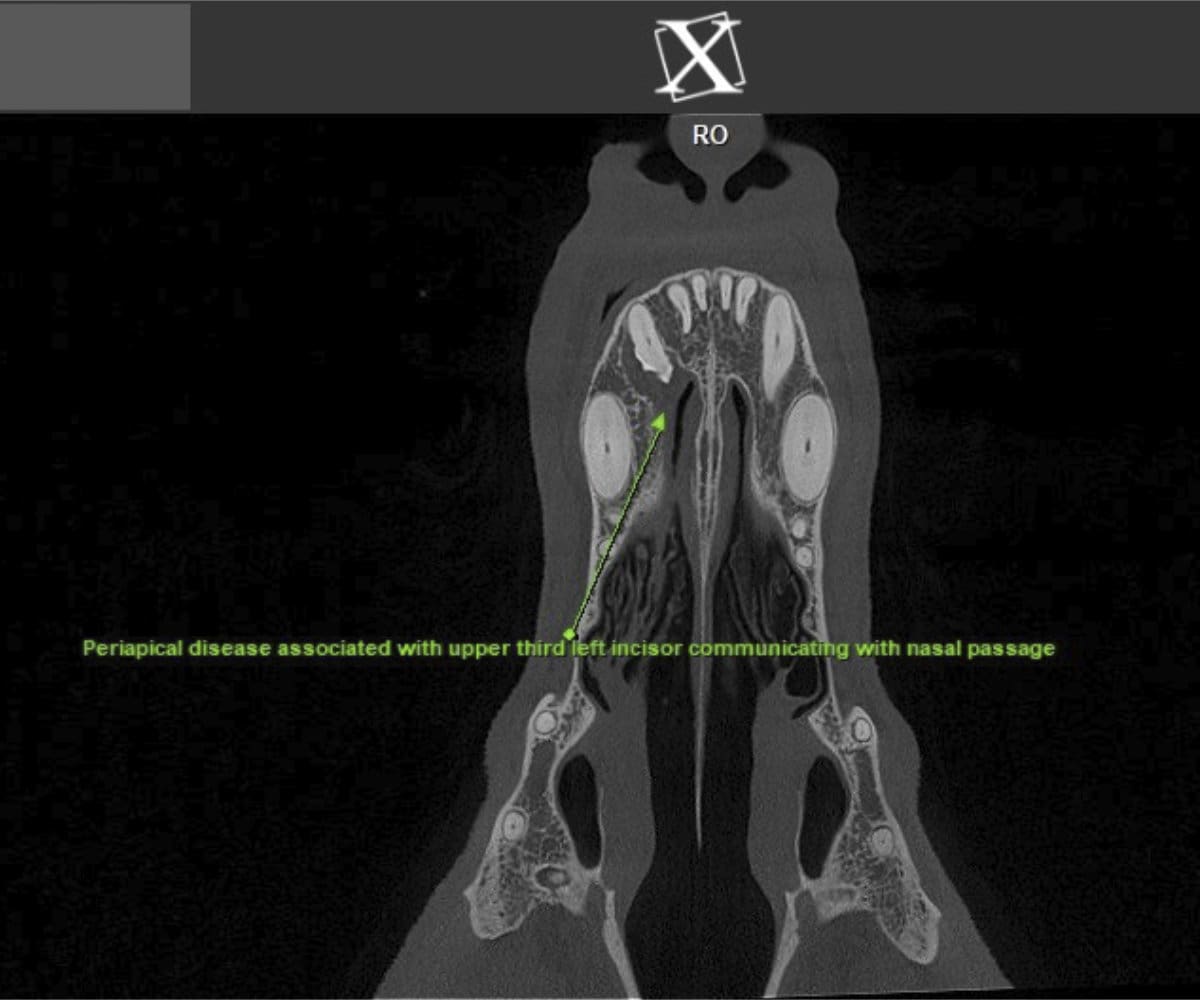

In addressing these limitations, CBCT emerges as a pivotal advancement. Conducting a CBCT scan on our patients is characterized by minimal time and effort, effectively reducing anesthesia duration. Moreover, this technology facilitates the generation of a comprehensive 3D reconstruction of the teeth and skull, surpassing the constraints of traditional radiographs. This innovative approach empowers our veterinary professionals to identify oral pathologies that may have been missed on traditional radiographs.

Cone beam CT technology provides veterinarians with 3-dimensional images in far greater detail than dental radiographs. CBCT scans significantly decrease the amount of time a patient spends under anesthesia compared to the time it takes to complete dental radiographs.

Our CBCT VetCAT unit is easily rolled up to our treatment table and takes only 40 seconds to complete a scan. It has proven to be invaluable in the diagnosis and treatment planning for pets with periodontal, endodontic and cancerous disease conditions. It is also indispensable in the evaluating our trauma cases with jaw fractures.